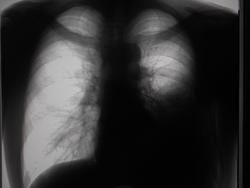

Пол пациента: Мужской пол Тип патологии: Другое Область исследования: Грудная клетка и верхние дыхательные пути Методы исследования: Rg Мужчина, 1983 года рождения, наркоман. Жалобы на затруднение дыхания, больше толком ничего не может сказать. Поставила просто показать, наверное это осумкованный плеврит, но очень уж форма причудливая) https://radiomed.ru/sites/default/files/styles/case_slider_image/public/user/16049/dscn0196-2.jpg?itok=VMOIZfz8 https://radiomed.ru/sites/default/files/styles/case_slider_image/public/user/16049/dscn0200-2.jpg?itok=jF8RVB_8 https://radiomed.ru/sites/default/files/styles/case_slider_image/public/user/16049/dscn0199-2.jpg?itok=d8mgQYPQ ID:25338 Пнд, 24/12/2012 - 21:04 #1 Катенёв Валенти... Не на сайте Был на сайте: 7 лет 2 недели назад Зарегистрирован: 22.03.2008 - 22:15 Публикации: 54876 Здравствуйте Мила! Задний паракостальный без сомнений! Пнд, 24/12/2012 - 23:58 #2 Наталия Васильевна Не на сайте Был на сайте: 5 лет 8 месяцев назад Зарегистрирован: 25.09.2011 - 09:02 Публикации: 754 Катенёв Валентин Львович wrote: Здравствуйте Мила! Задний паракостальный без сомнений! Согласна, вопрос как давно? Если процесс "свеженький"-может, пардон, шарахнуть в эмпиему в любой момент. Втр, 25/12/2012 - 01:11 #3 И.Бондаренко Не на сайте Был на сайте: 2 дня 13 часов назад Зарегистрирован: 13.09.2011 - 22:55 Публикации: 9206 Наталия Васильевна wrote: Катенёв Валентин Львович wrote: Здравствуйте Мила! Задний паракостальный без сомнений! Согласна, вопрос как давно? Если процесс "свеженький"-может, пардон, шарахнуть в эмпиему в любой момент. Пусть хирурги "шарахнут" пункцией. Тогда точно будете знать. Втр, 25/12/2012 - 03:06 #4 Mila85 Не на сайте Был на сайте: 3 года 1 месяц назад Зарегистрирован: 15.03.2012 - 16:59 Публикации: 1790 Катенёв Валентин Львович wrote: Здравствуйте Мила! Задний паракостальный без сомнений! Здравствуйте, мы на работе тоже так единогласно подумали. Давность неизвестна, пациент где-то частно наблюдается со своей зависимостью, туда и потопал

Задний паракостальный без сомнений!

Согласна, вопрос как давно? Если процесс "свеженький"-может, пардон, шарахнуть в эмпиему в любой момент.